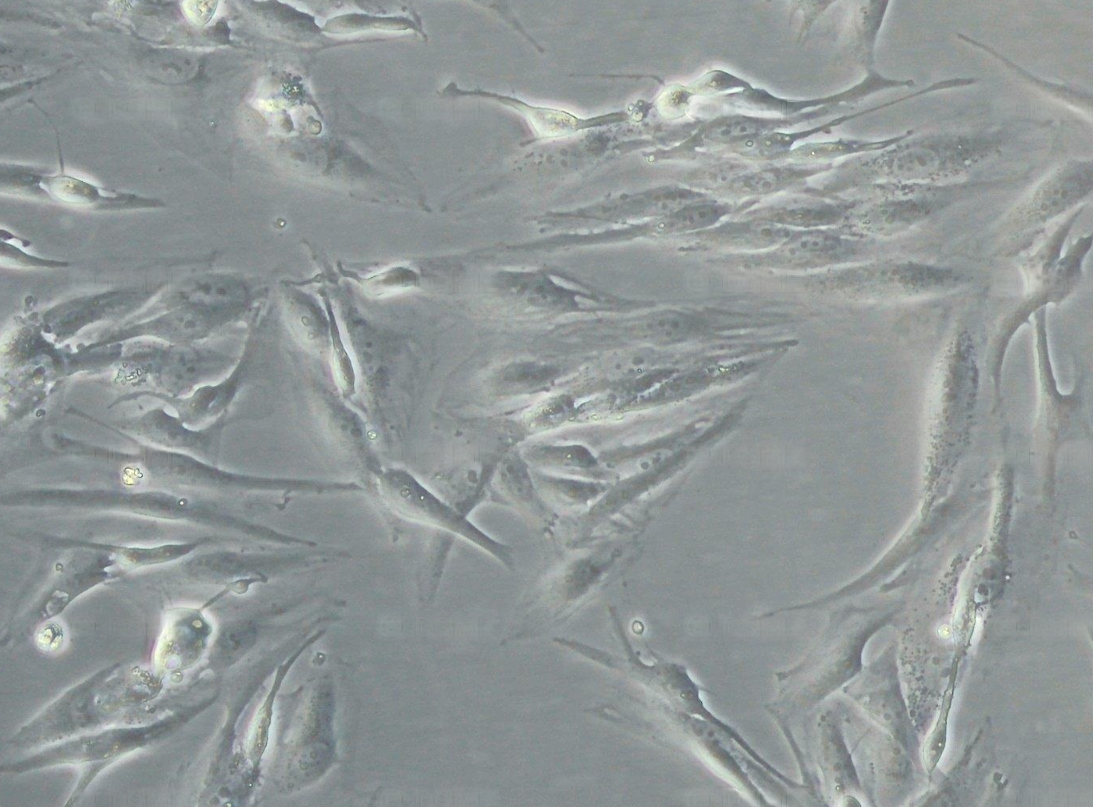

形態(tài) |

上皮細胞樣 |

生長特征 |

貼壁生長 |